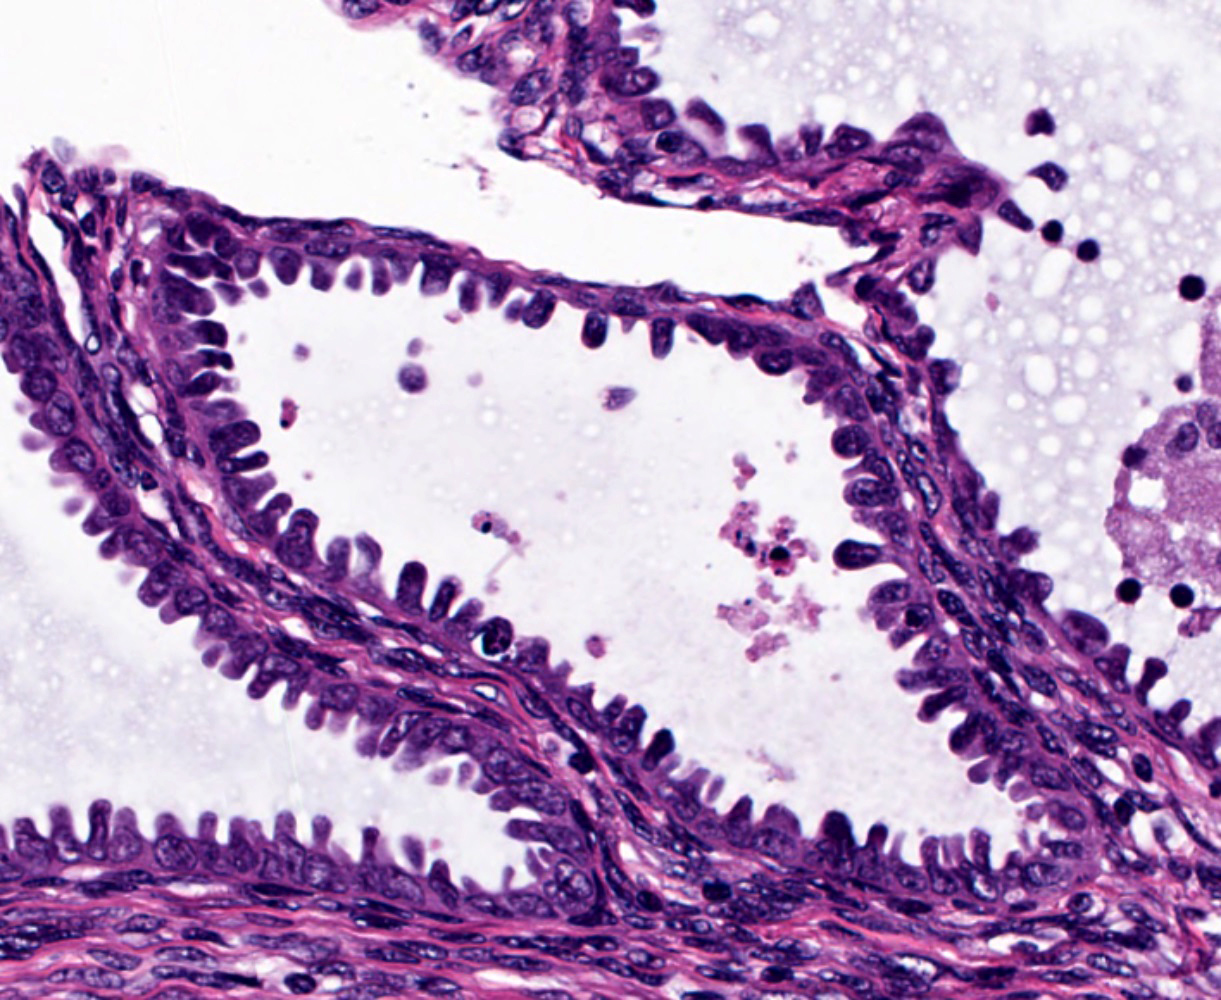

Microscopic (histologic) images

Contributed by Jessica L. Bentz, M.D.

- Tubal metaplasia (Mod Pathol 2011;24:1254):

- Resembling fallopian tube epithelium; pseudostratified with ciliated eosinophilic cells and clear round cells